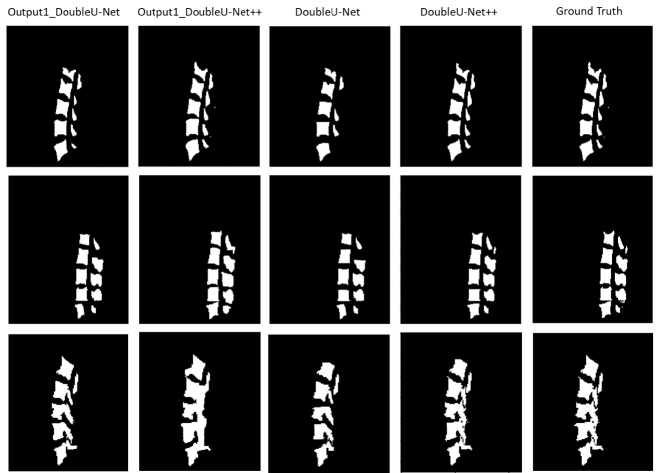

Moreover, the segmentation results generated by DoubleU-Net and DoubleU-Net++ are provided in Figure 7 and Figure 8 for VerSe2020 and xVertSeg datasets, respectively. Each row depicts an image on sagittal view. The first and second columns show the segmented image, described in Section 3.3.2 (Figure 3), and the third and fourth columns illustrate the final output of DoubleU-Net and DoubleU-Net++, respectively. Compared with DoubleU-Net the final outputs of DoubleU-Net++are more close to the ground truth which is shown in the last column.